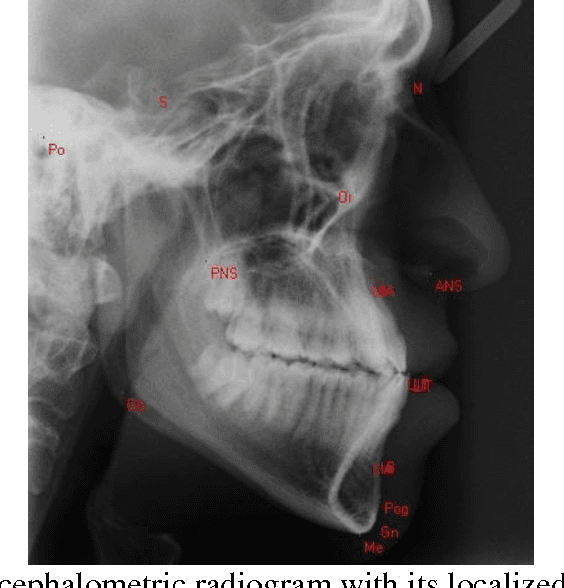

Abstract:Cephalometric analysis has an important role in dentistry and especially in orthodontics as a treatment planning tool to gauge the size and special relationships of the teeth, jaws and cranium. The first step of using such analyses is localizing some important landmarks known as cephalometric landmarks on craniofacial in x-ray image. The past decade has seen a growing interest in automating this process. In this paper, a novel hybrid approach is proposed for automatic detection of cephalometric landmarks. Here, the landmarks are categorized into three main sets according to their anatomical characteristics and usage in well-known cephalometric analyses. Consequently, to have a reliable and accurate detection system, three methods named edge tracing, weighted template matching, and analysis based estimation are designed, each of which is consistent and well-suited for one category. Edge tracing method is suggested to predict those landmarks which are located on edges. Weighted template matching method is well-suited for landmarks located in an obvious and specific structure which can be extracted or searchable in a given x-ray image. The last but not the least method is named analysis based estimation. This method is based on the fact that in cephalometric analyses the relations between landmarks are used and the locations of some landmarks are never used individually. Therefore the third suggested method has a novelty in estimating the desired relations directly. The effectiveness of the proposed approach is compared with the state of the art methods and the results were promising especially in real world applications.